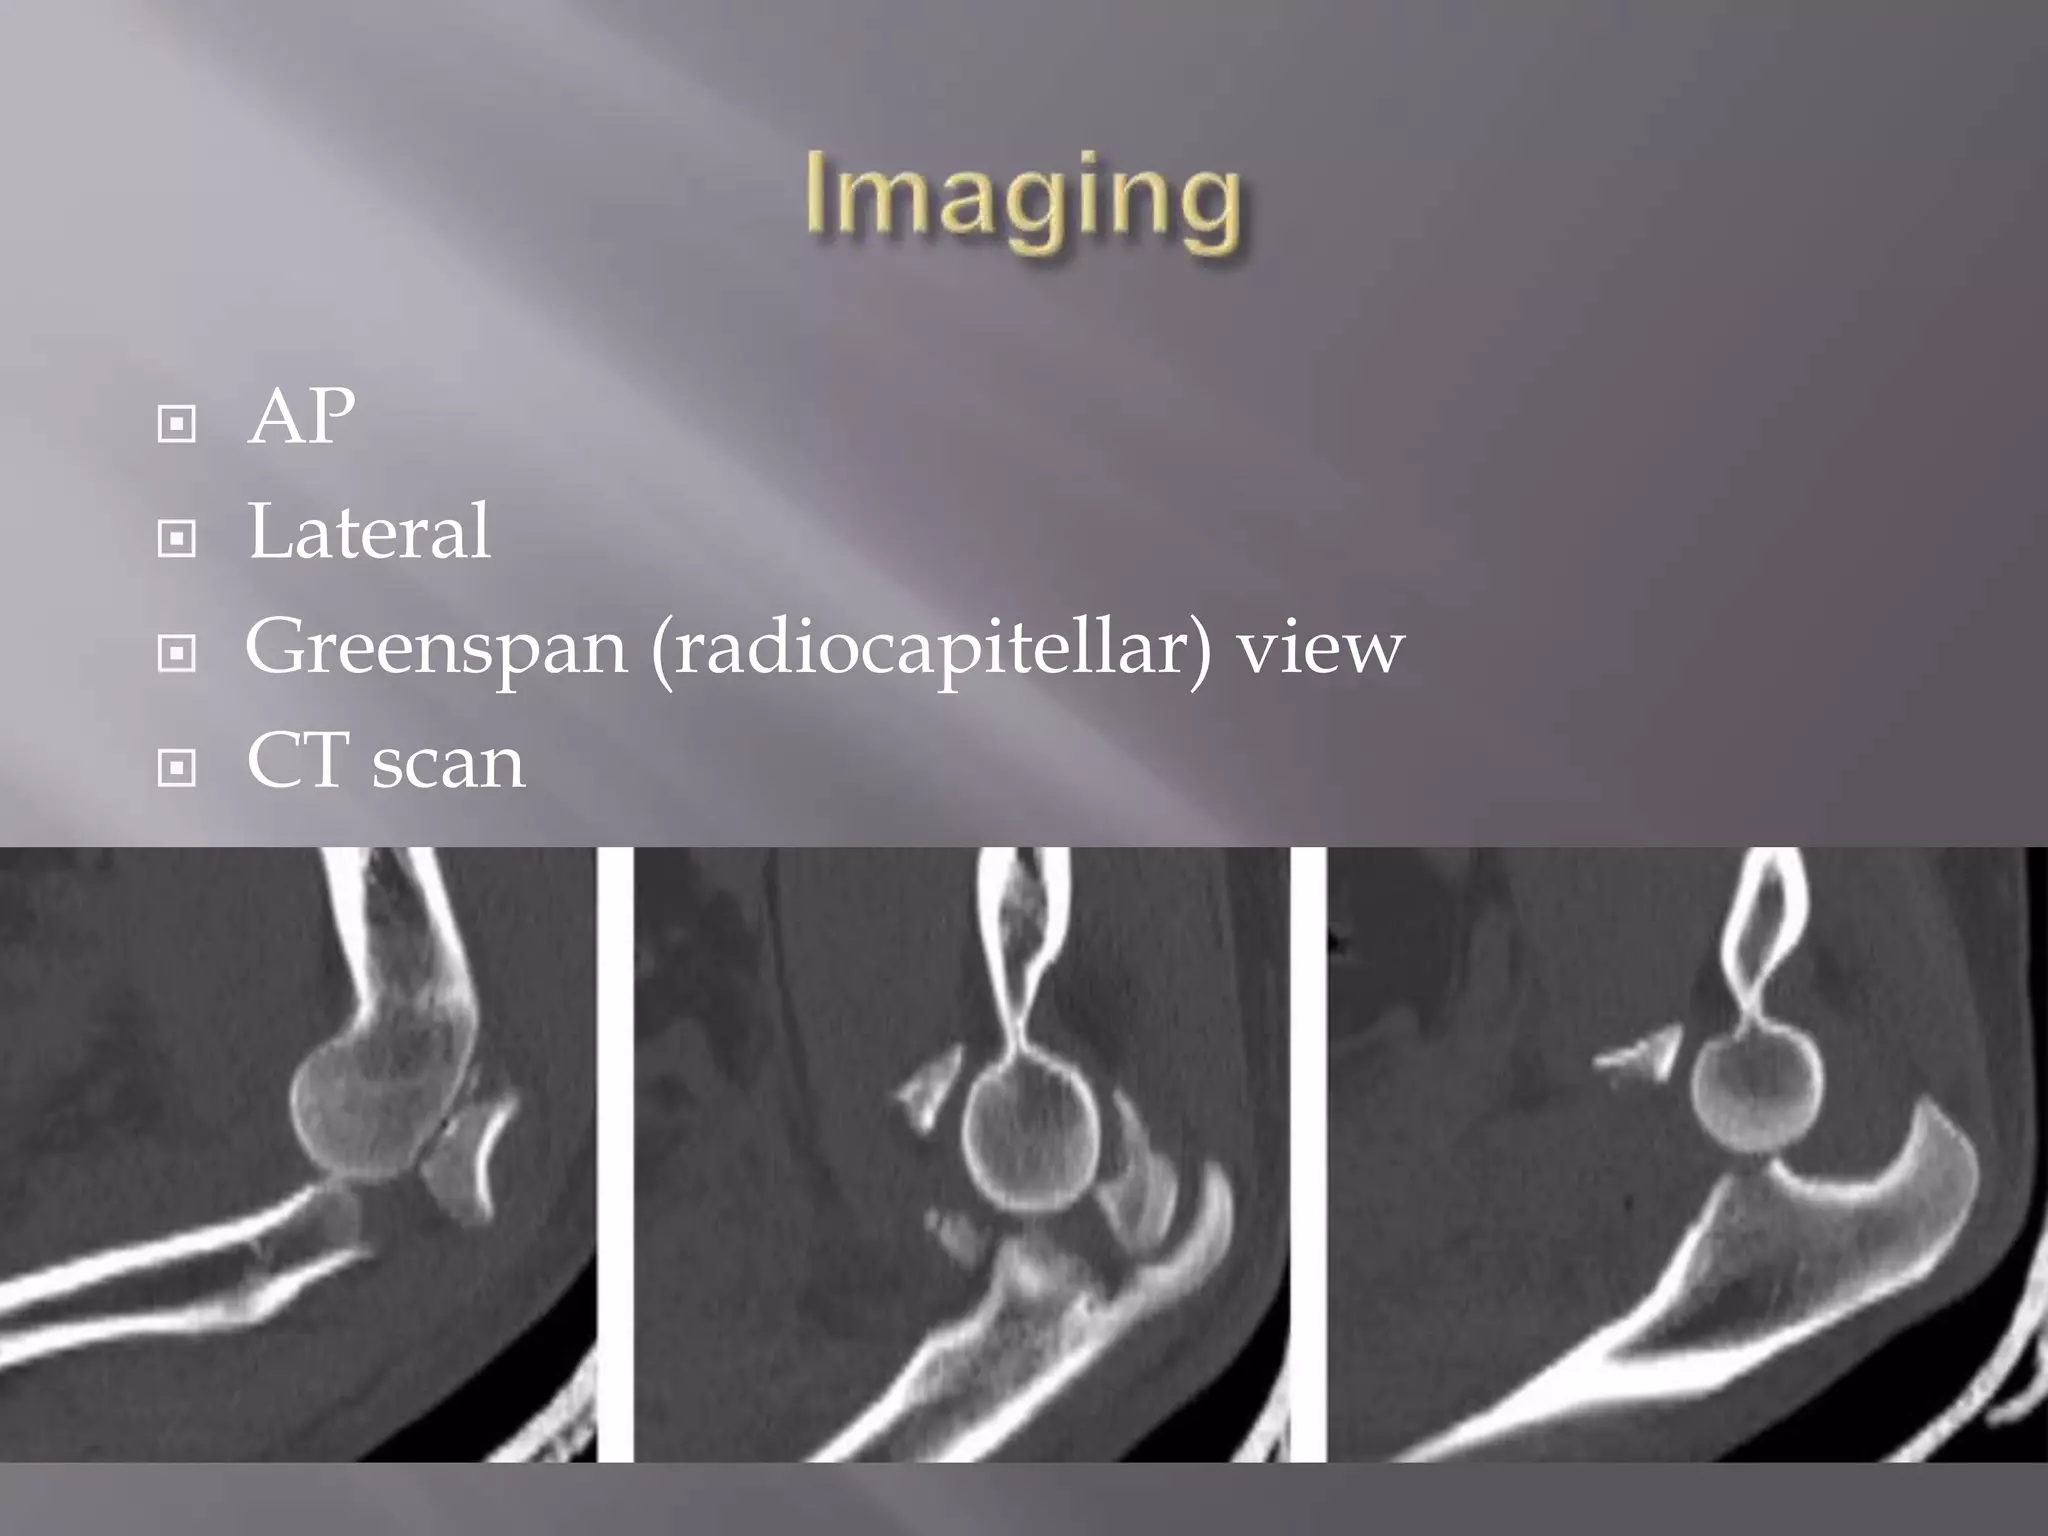

This document discusses the terrible triad injury of the elbow, which involves fractures of the radial head, coronoid process, and posterolateral dislocation. It notes the poor outcomes associated with this injury like stiffness, instability, and hardware failure. The document outlines the relevant anatomy of the medial collateral ligament and lateral uncular collateral ligament. It describes the mechanism of injury, known as the fall on an outstretched hand, and how the ligaments and capsule fail in this injury. Diagnostic imaging and classification of radial head and coronoid fractures are covered. Treatment options including observation, resection, open reduction internal fixation, and replacement are presented. Surgical approaches and techniques are also outlined.